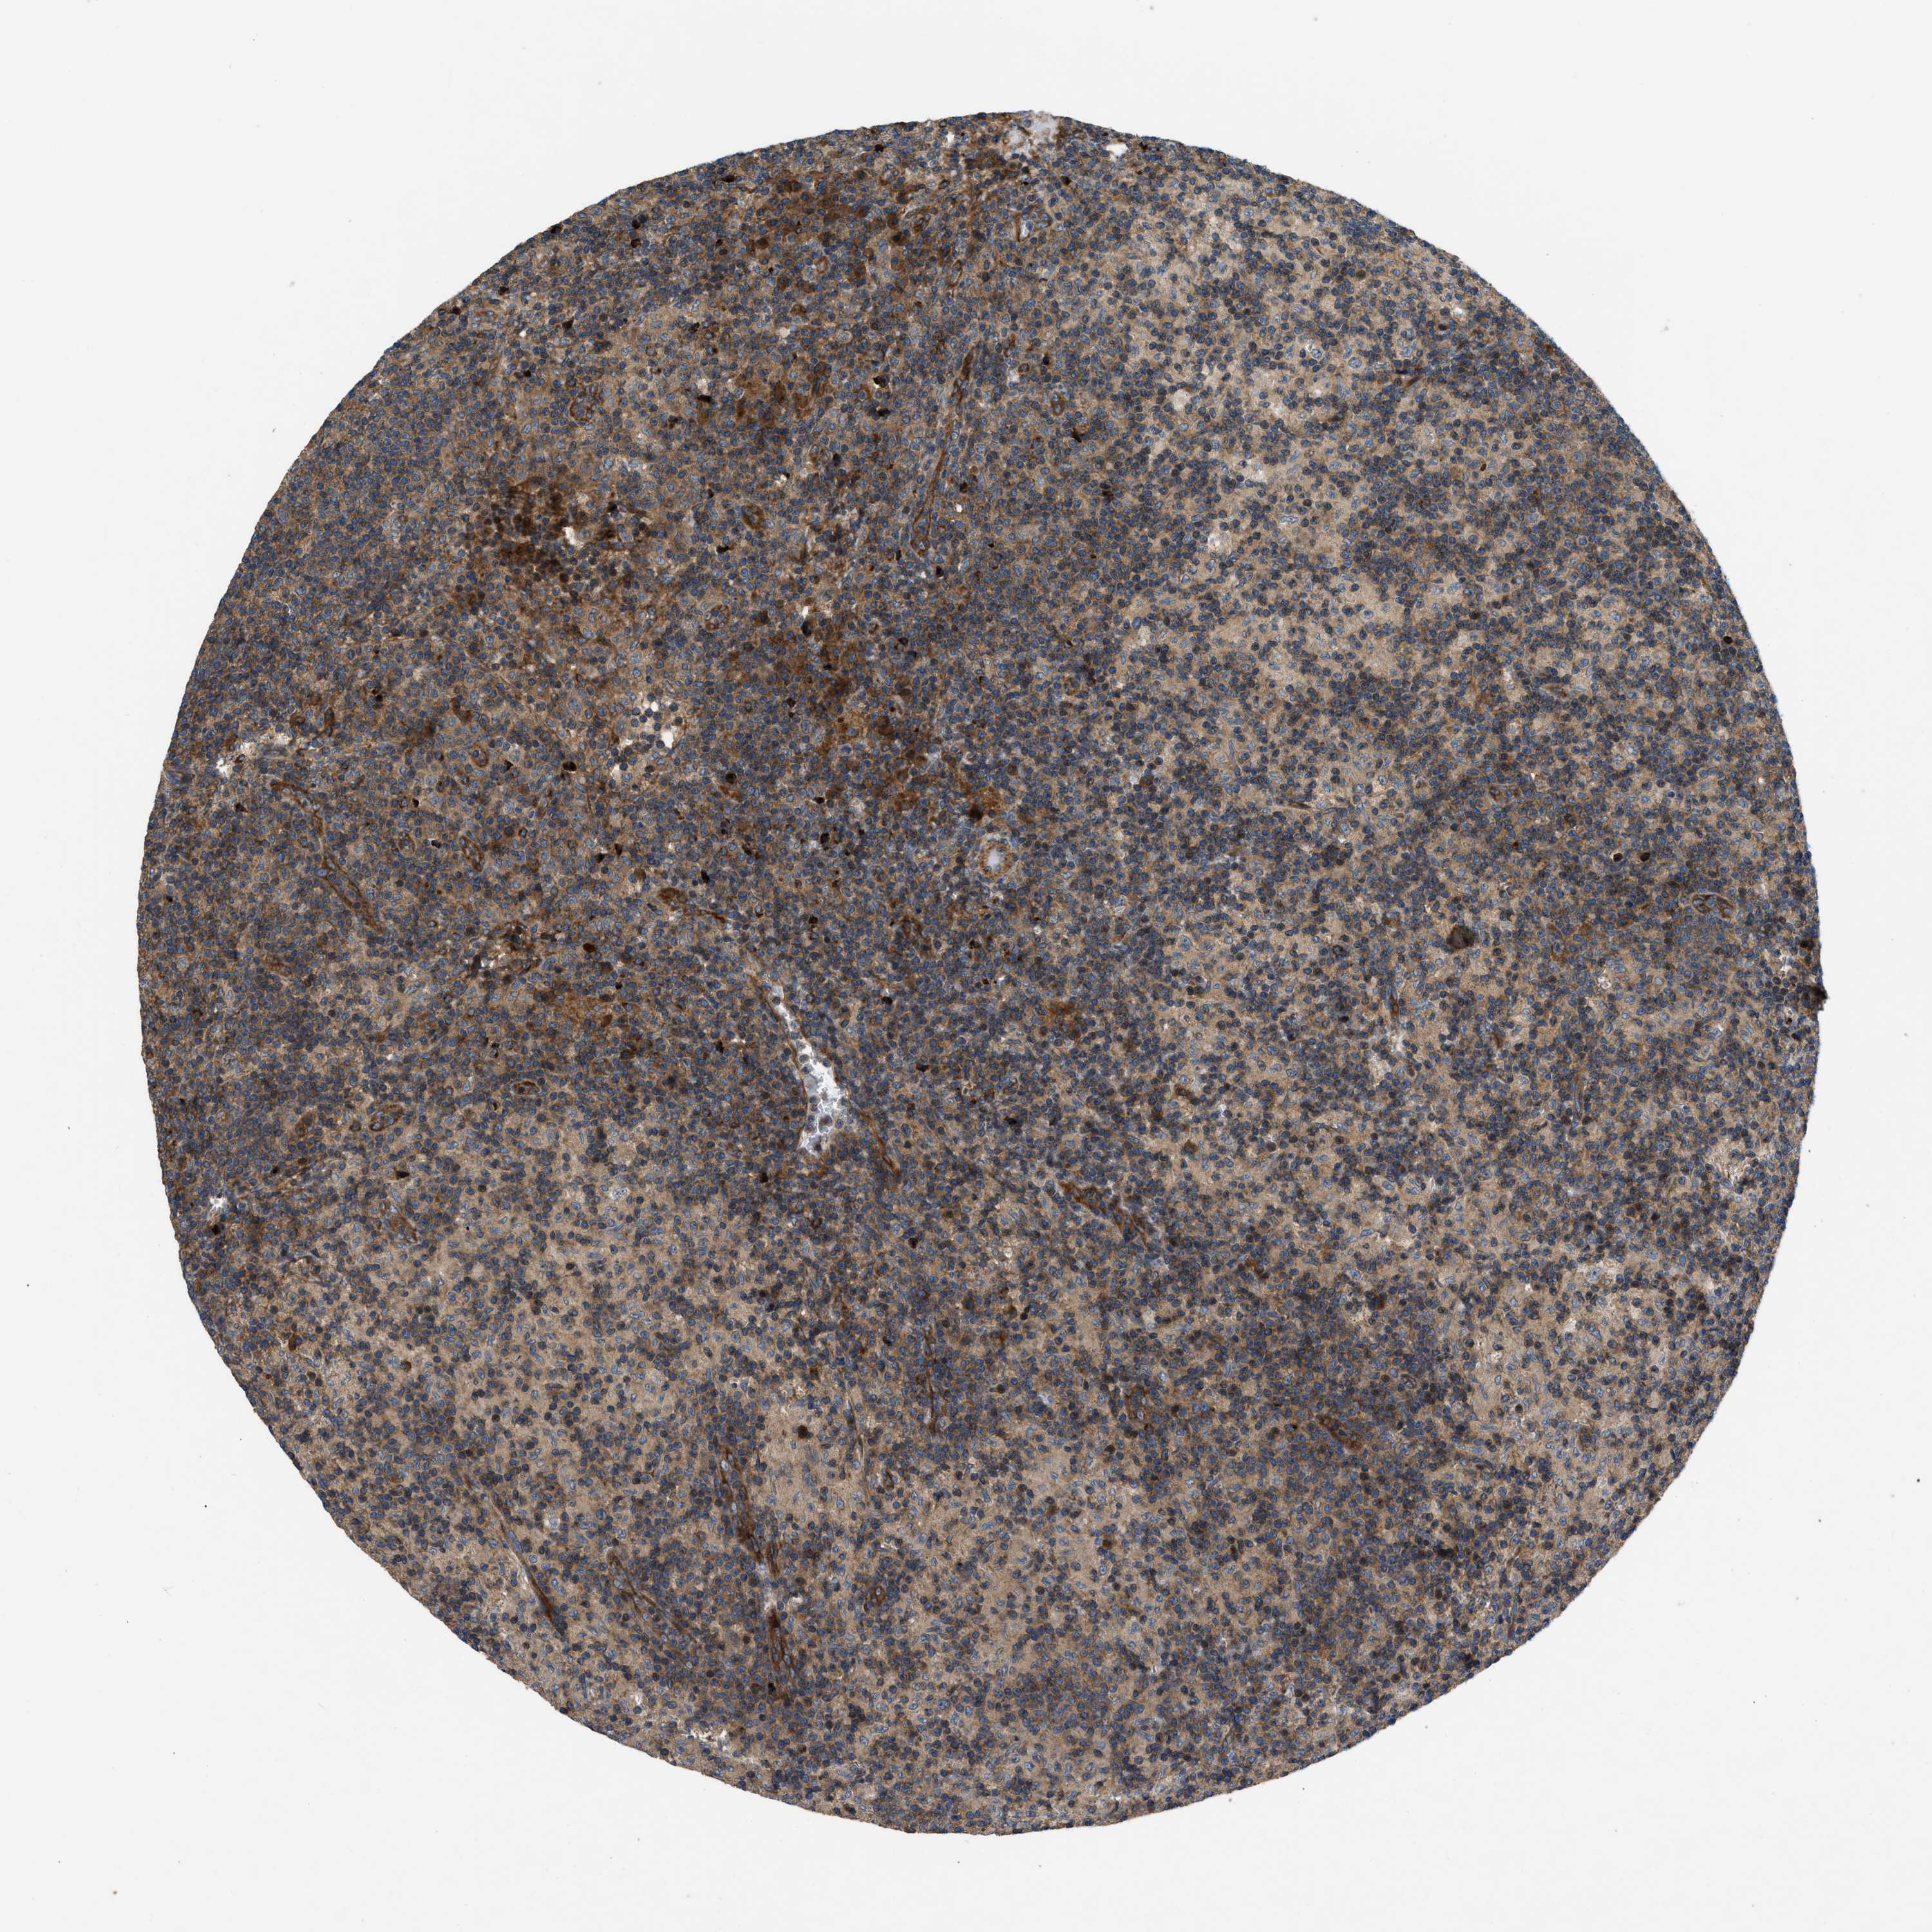

LYMPH NODE

Lymphoid tissue